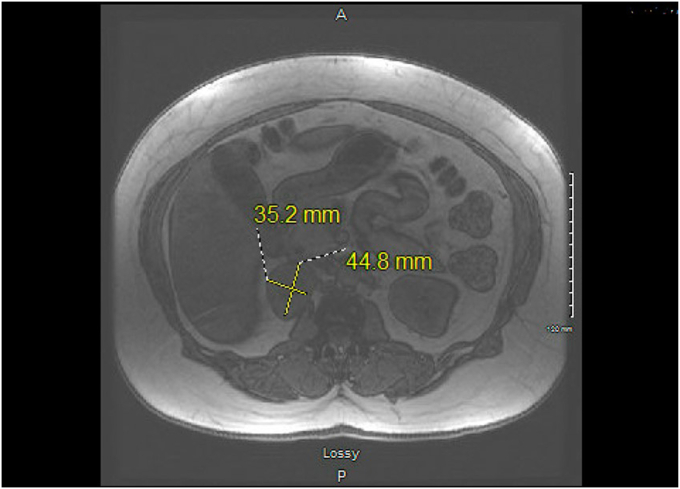

Patient 1 and patient 2 were 35-year-old and 45-year-old woman, respectively. Patient 1 presented with a history of controlled hypertension and symptoms of anxiety along with palpitations, diaphoresis, and flushing. Patient 2 complained of abdominal pain and underwent abdominal computed tomography (CT) imaging. Patient 1 and patient 2 had metanephrine levels of 76 pg/mL and 61 pg/mL (normal <57 pg/mL), respectively, and normetanephrine levels of 161 pg/mL and 116 pg/mL (normal < 148 pg/mL), respectively. CT scans depicted right adrenal masses in both cases: patient 1 had a 2.3 × 2.6 cm mass measuring 36 Hounsfield units on noncontrast CT imaging and patient 2 had a 4.5 × 3.5 cm right adrenal mass measuring 73 Hounsfield units on contrast CT imaging. Both patients underwent laparoscopic robotic adrenalectomies without complications. The pathologic analyses of both cases revealed composite pheochromocytoma-ganglioneuroma tumors. Surveillance at 1 year in both patients demonstrated no evidence of recurrence.